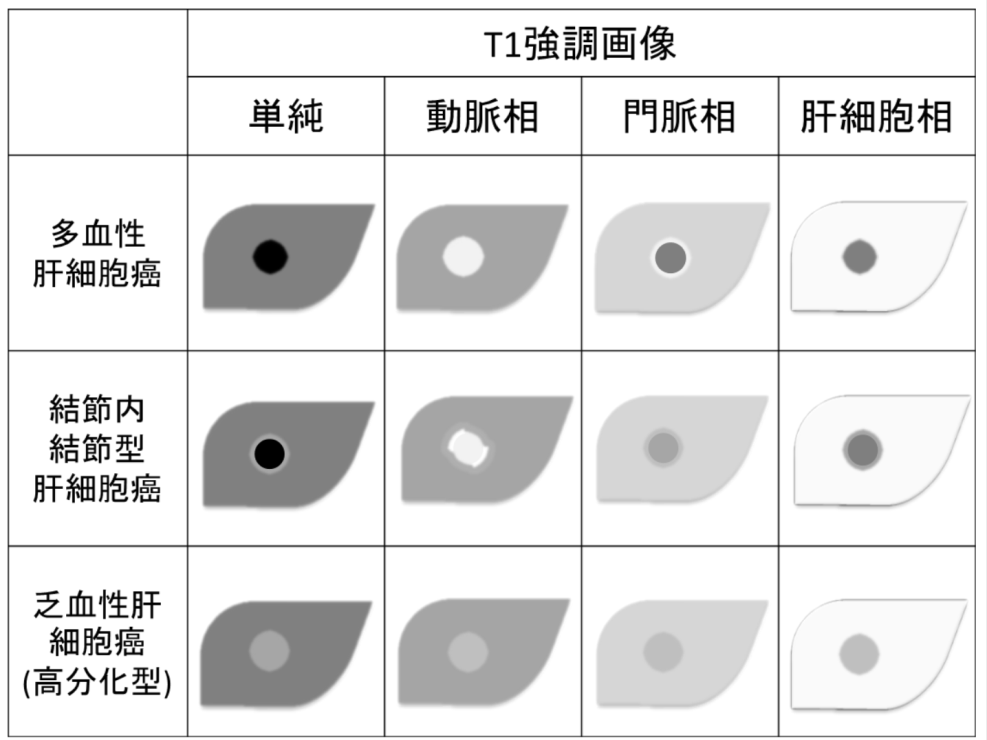

放射線技師向け kenminkei11. 2.MRIのパルスシーケンス 表在性軟部腫瘍では病変部位や形態が様々で あり,プロトコールを標準化しづらい.当院で 表在性軟部腫瘍の画像診断 391 図1石灰化上皮腫 (a)(b)(c)後背部正中の皮下腫瘤は,MRIのT1強調像,T2強調像でともに低信号で辺縁に. 肝細胞癌はt2強調画像、拡散強調画像で高信号、t 1 強調画像では低信号を呈している。造影ダイナミック検査早期相ではgd.

MRI ・T2強調像でのjunctional zone. 15分で分かる(?)MRI 古典力学的説明※1 MRI原理へのいざないPart 1 1個のプロトンから15分単位で理解できる(?) 基本的な信号強度 Part 1 プロトン密度、T1、T2と信号強度 ※学部学生は最低でもPart 1を理解すること. 4.mri:撮像法と画像所見 角谷 眞澄 藤永 康成 はじめに 肝疾患の診断にmriが期待されるのは,その優れた 組織コントラスト能によるところが大きい.t1強調像, t2強調像にて肝細胞性結節性病変は様々な信号強度を.

上腹部mriの見方 シーケンスを4つに分類しよう 画像診断 Com